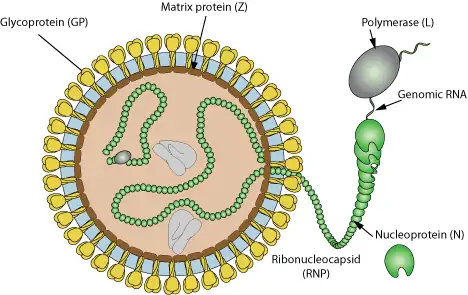

拉沙病毒属于沙粒病毒科(Arenaviridae),这个名称源于拉丁语"arena",意为"沙子"。在电子显微镜下,病毒颗粒内部可见散布的核糖体颗粒,状如沙粒,这正是其名称的由来。

拉沙病毒是一种有包膜的单链RNA病毒,其基因组分为两个节段:L节段(约7.5千碱基)和S节段(约3.5千碱基)。这两个节段采用独特的双向编码策略,每个节段都编码两个不同的蛋白质。L节段编码RNA依赖性RNA聚合酶(L蛋白)和锌指蛋白(Z蛋白),而S节段则编码核蛋白(NP)和糖蛋白前体(GPC)。

病毒表面的糖蛋白复合物是入侵宿主细胞的钥匙。它由三个部分组成:稳定的信号肽(SSP)、受体结合亚基(GP1)和跨膜融合亚基(GP2)。当病毒通过α-营养不良聚糖受体进入细胞后,它会利用宿主细胞的机制进行复制,产生新的病毒颗粒。

电子显微镜下的拉沙病毒呈现出典型的沙粒病毒特征:球形或有包膜颗粒,直径从60到300纳米不等,大小差异显著。病毒颗粒从宿主细胞表面出芽释放,这一过程由Z蛋白介导。病毒的生命周期完全在细胞质中进行,从吸附、入侵、转录、复制到组装和释放,每一个环节都精密调控。